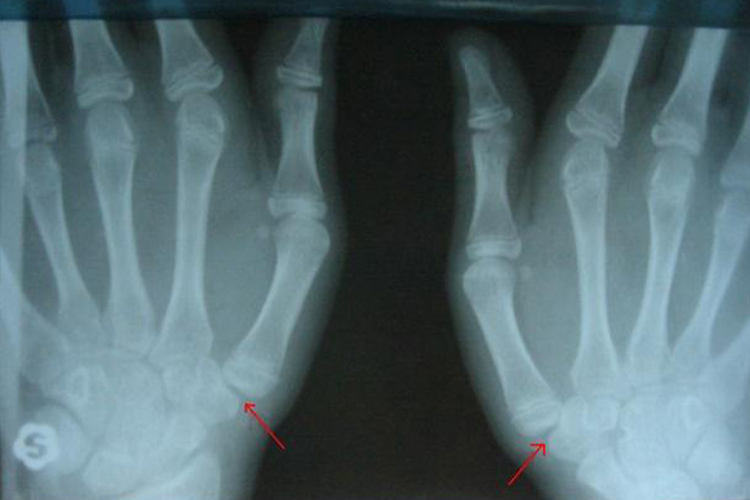

第一腕掌关节脱位表现为手背部肿胀、疼痛、拇指活动受限;腕背侧压痛,第1掌骨头叩击痛,同时有松脱感,在腕背侧可触及骨端隆起畸形。通过X线检查,可以观察到第一掌腕关节面平行排列关系丧失。